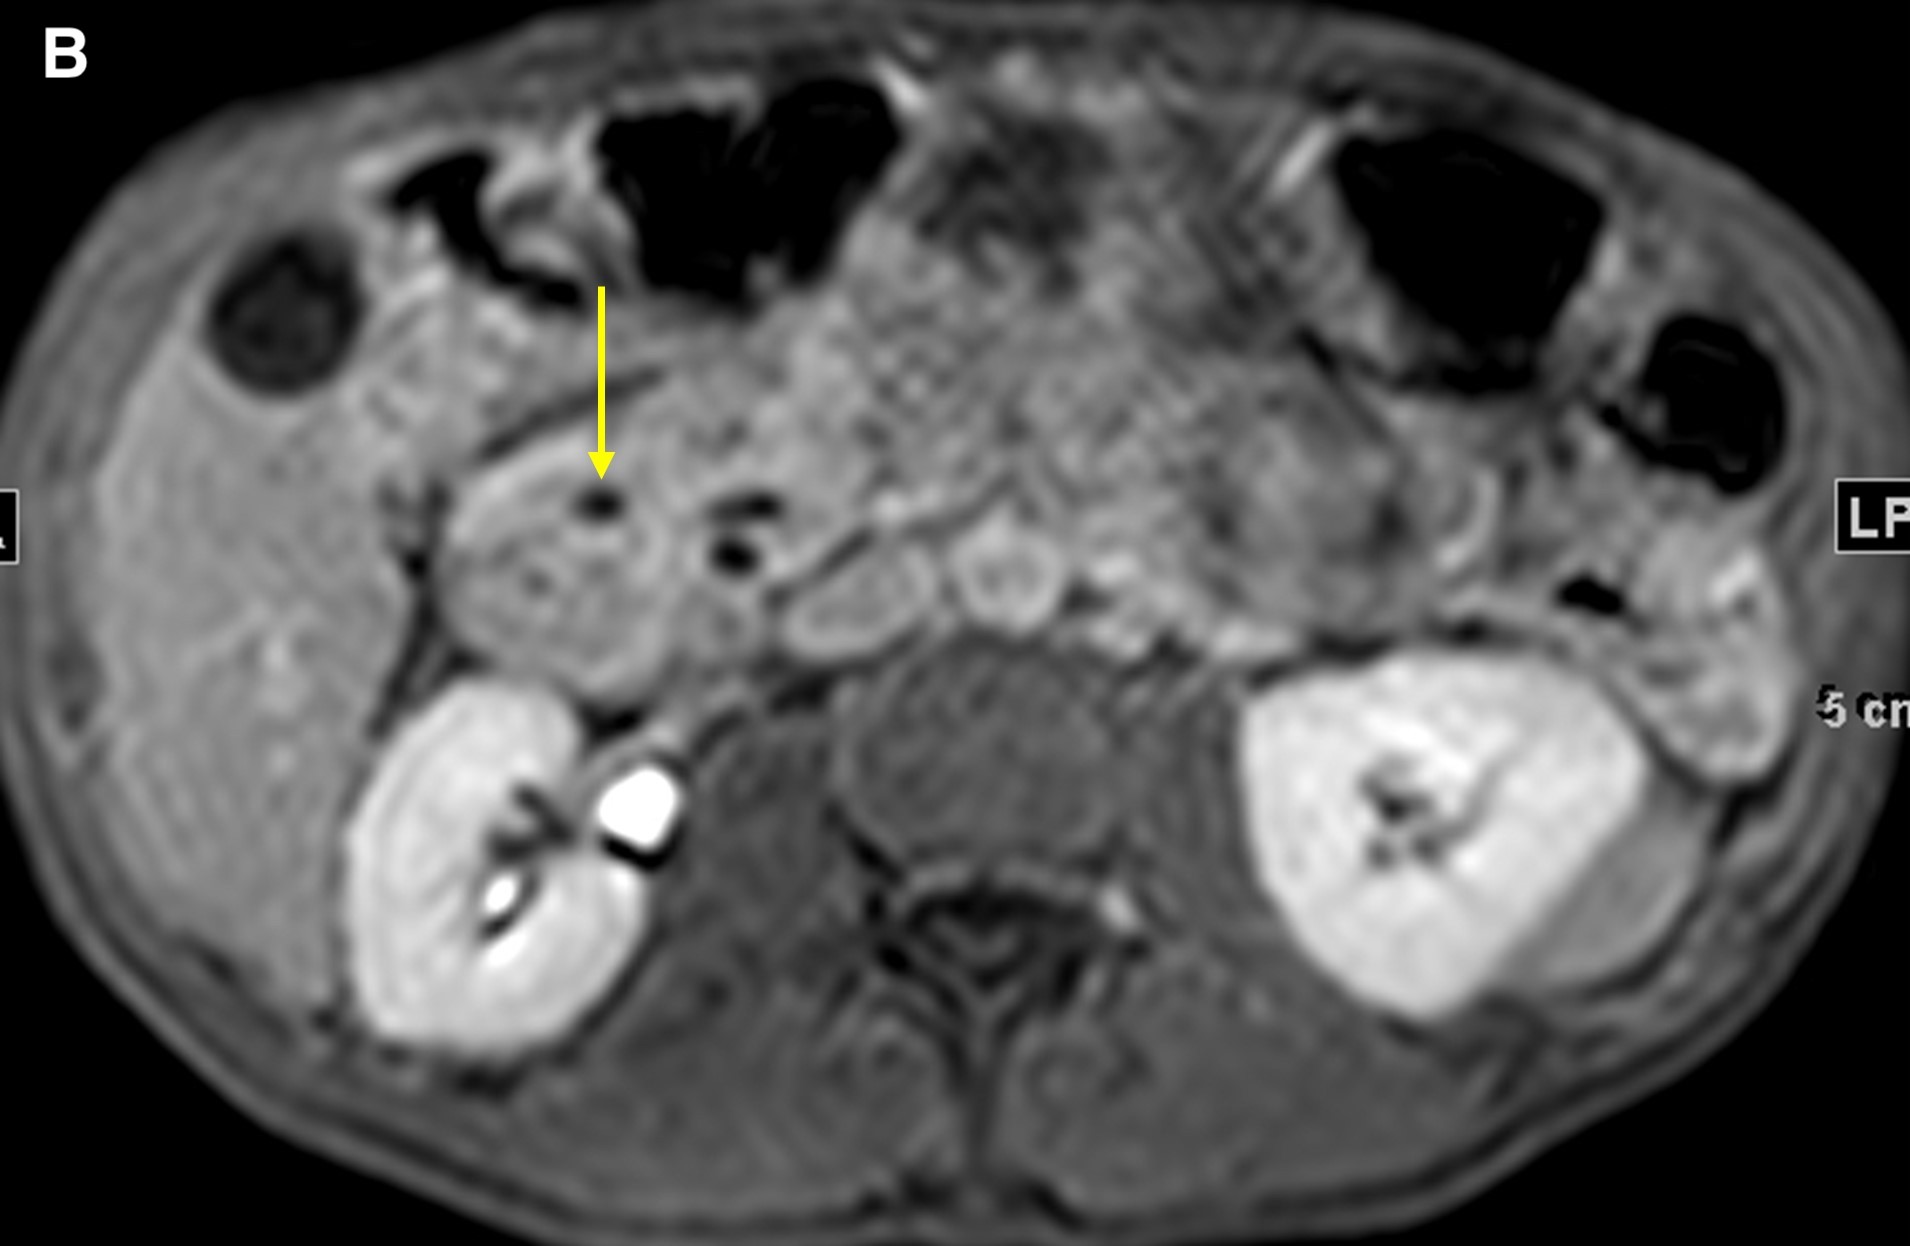

On magnetic resonance imaging (MRI) scans, groove pancreatitis often shows a T1 hypointense “sheet like” mass in the groove space.6 Depending on timing, T2 can demonstrate hypointensity, isointensity, or hyperintensity in this region.1 The initial phase of disease shows T2 hyperintensity, with progression into isointensity or hypointensity caused by fibrosis as the disease course continues.1 Cysts or cystic masses can be seen in the duodenal wall or groove space in T2-weighted imaging, as we saw in our patient (Figure 3).1 Magnetic resonance cholangiopancreatography can be helpful, as it can also demonstrate nonspecific signs such as common bile duct/pancreatic duct dilation.1 Gadolinium-enhanced images show delayed enhancement caused by fibrosis, as we saw in our patient (Figure 4). In one study, approximately 93% of patients showed patchy, late, post-gadolinium enhancement of the pancreas.7 In both the pure and segmental forms of groove pancreatitis, authors of one study found medial wall of the duodenum involvement with mural cysts on T2 weighted imaging.8 In cases of segmental groove pancreatitis, the common bile duct shows gradual tapering, while in cases of malignancy, the duct shows abrupt cutoff, which we saw in our patient (Figure 5).6

Figure 5. A coronal T2WI demonstrated gradual tapering of the dilated common bile duct, with the thickened wall of the duodenum (a, short arrow) and the soft tissue thickening in the groove region around the ampulla (a, long arrow). The maximum-intensity projection reconstruction of the magnetic resonance cholangiopancreatography demonstrated dilated intrahepatic ducts, smooth tapering of the common bile duct (b, short arrow), dilated pancreatic duct, and narrowing of the lumen of the duodenum due to wall thickening (b, long arrow).